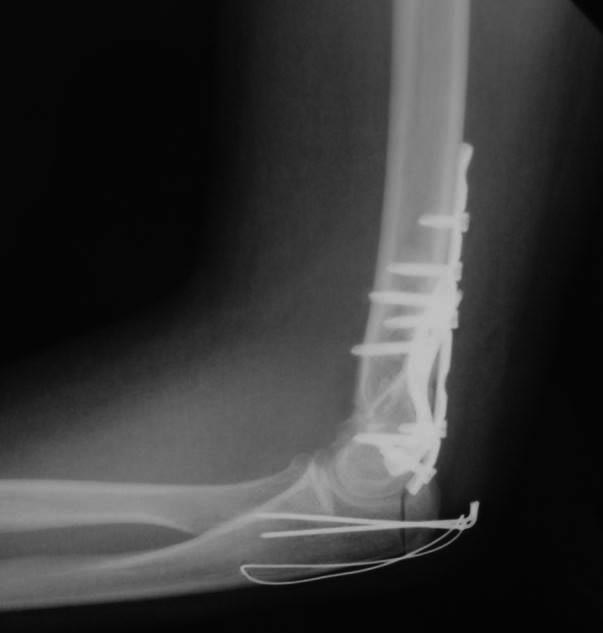

[Ortho] Перелом плечевой и головки лучевой костей (и немного локтевой)

Как обещал, выкладываю послеоперационные (на следующий день после

операции) фото. Заранее прошу слишком проксимальную остеотомию локтевого

отростка не ругать. Обычно делаю дистальнее.